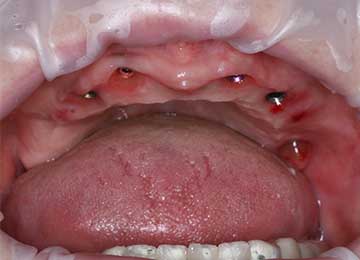

Имплантация зубов: фото "До" и "После"

Фото ДО

Фото ПОСЛЕ

Наведите для просмотра

All-on-4